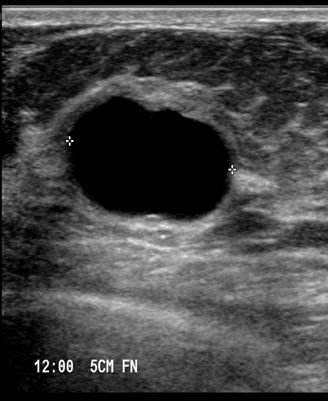

Συνήθως είναι ασυμπτωματικές ή αποτελούν τυχαίο εύρημα σε έλεγχο με υπερηχογράφημα. Σε περίπτωση που μεγαλώσουν πολύ μπορούν να γίνουν αντιληπτές με την ψηλάφηση ως ογκίδιο, ευκίνητο και ανώδυνο, με ομαλή παρυφή. Σπανιότερα μπορεί να συνυπάρχει πόνος, ευαισθησία στην ψηλάφηση ή αύξηση του μεγέθους λίγο πριν την έμμηνο ρύση . Δεν είναι ασυνήθιστη η έκκριση ενός καθαρού, αχυρόχρωου (κίτρινου) ή σκούρου καφέ υγρού από τη θηλή.

Απεικονιστικές εξετάσεις